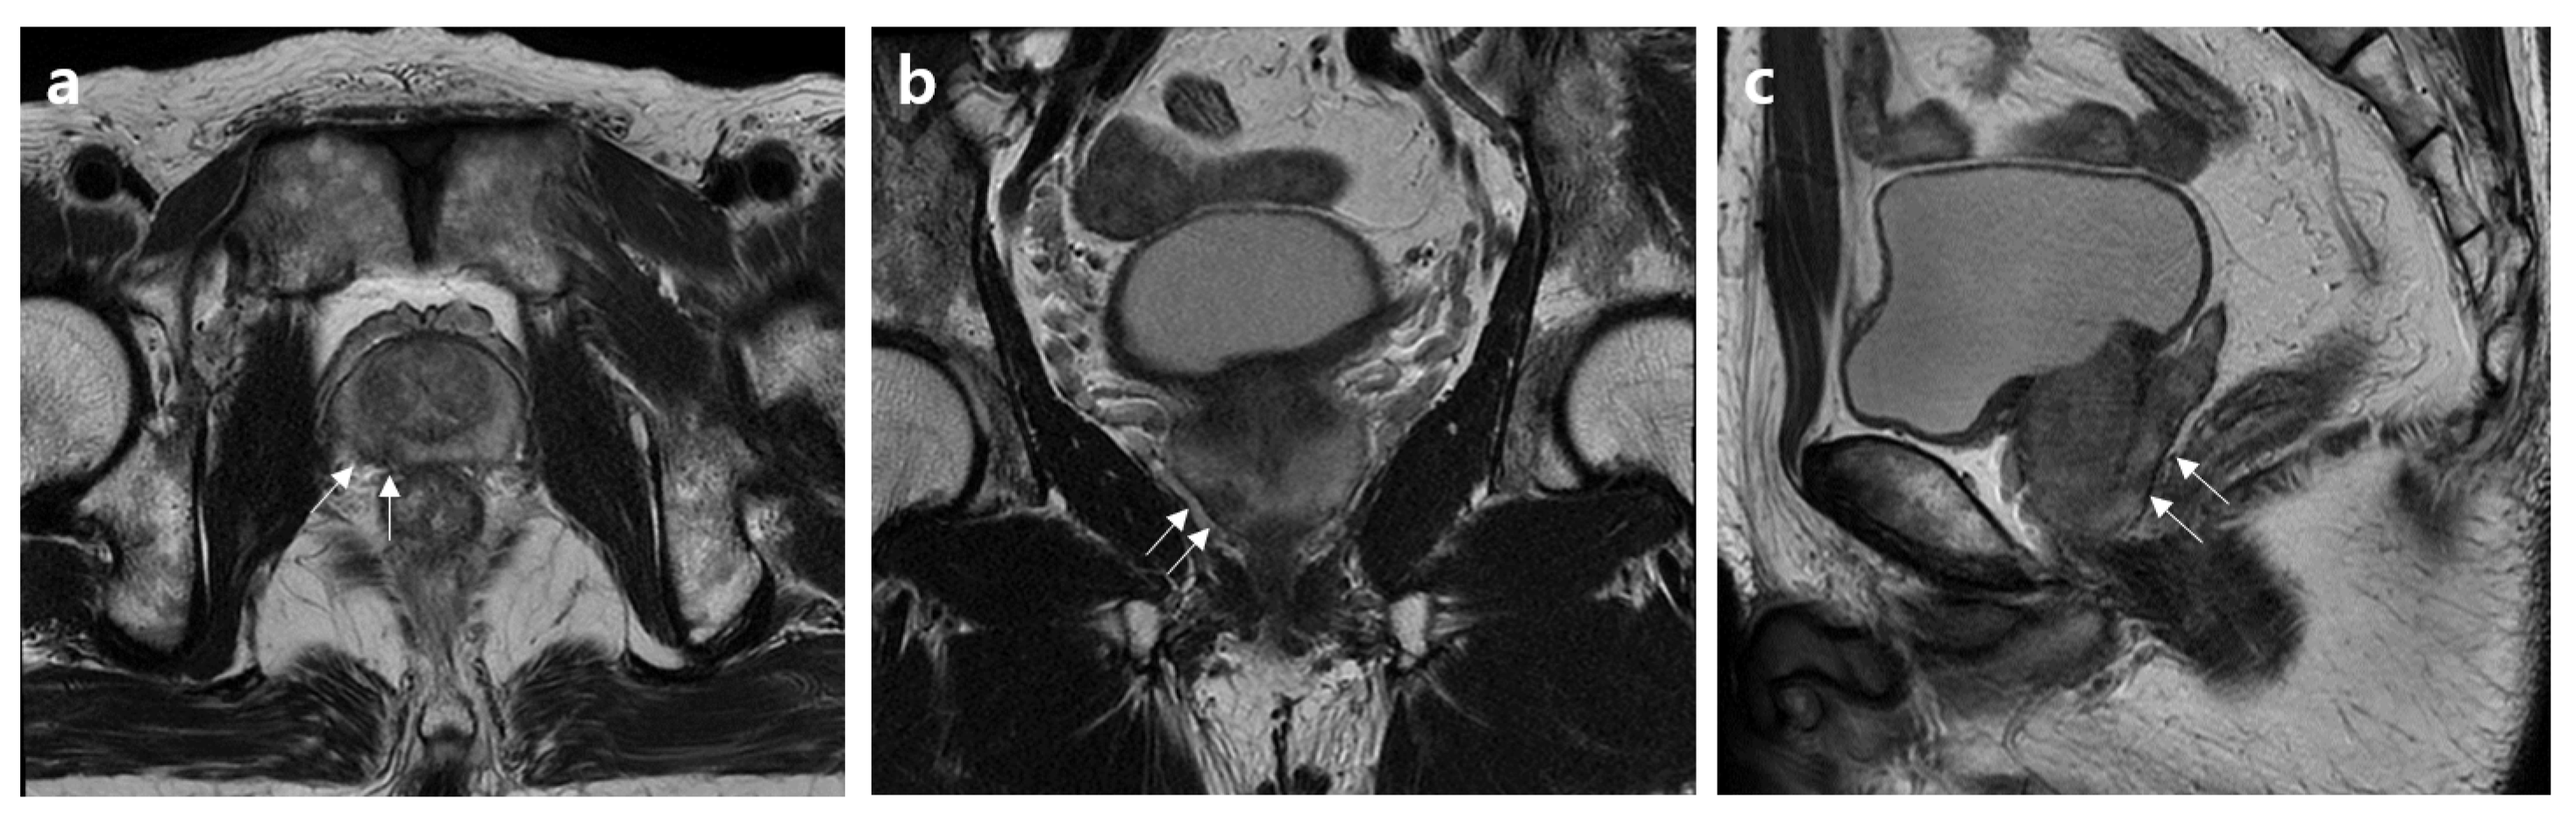

2.2. MRI Assessment